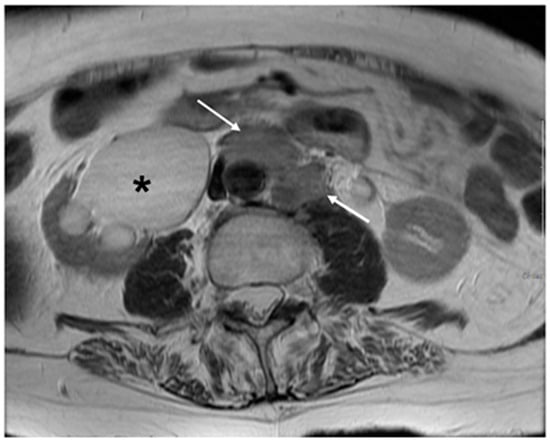

6. FIGO Stage III

- Kostov, S.; Selçuk, I.; Watrowski, R.; Kornovski, Y.; Yalçın, H.; Slavchev, S.; Ivanova, Y.; Dzhenkov, D.; Yordanov, A. Pelvic Sidewall Anatomy in Gynecologic Oncology-New Insights into a Potential Avascular Space. Diagnostics 2022, 12, 519. [Google Scholar] [CrossRef]

| Stage III | Involves the lower third of the vagina and/or extends to the pelvic wall and/or causes hydronephrosis or non-functioning kidney and/or involves pelvic and/or paraaortic lymph nodes |

| IIIB | Extension to the pelvic wall and/or hydronephrosis or non-functioning kidney (unless known to be due to another cause) |

| IIIC | Involvement of pelvic and/or paraaortic lymph nodes |